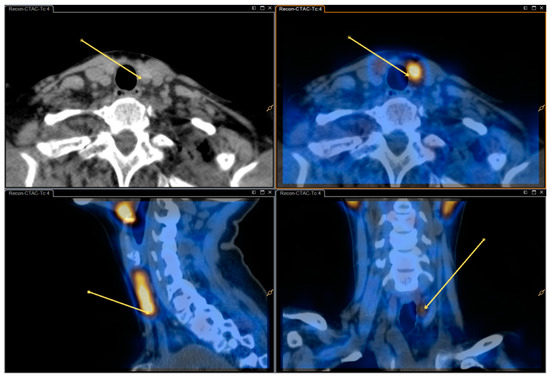

We report a case of 16-year-old female primary hyperparathyroidism patient who underwent cervical ultrasonography and 99mTc-sestamibi single photon emission computed tomography/computed tomography, both of which were negative for parathyroid adenoma. Subsequent 11C-methionine positron emission tomography/CT showed positive focal uptake suggesting parathyroid [...] Read more.

We report a case of 16-year-old female primary hyperparathyroidism patient who underwent cervical ultrasonography and 99mTc-sestamibi single photon emission computed tomography/computed tomography, both of which were negative for parathyroid adenoma. Subsequent 11C-methionine positron emission tomography/CT showed positive focal uptake suggesting parathyroid adenoma, which then was confirmed pathologically. Full article